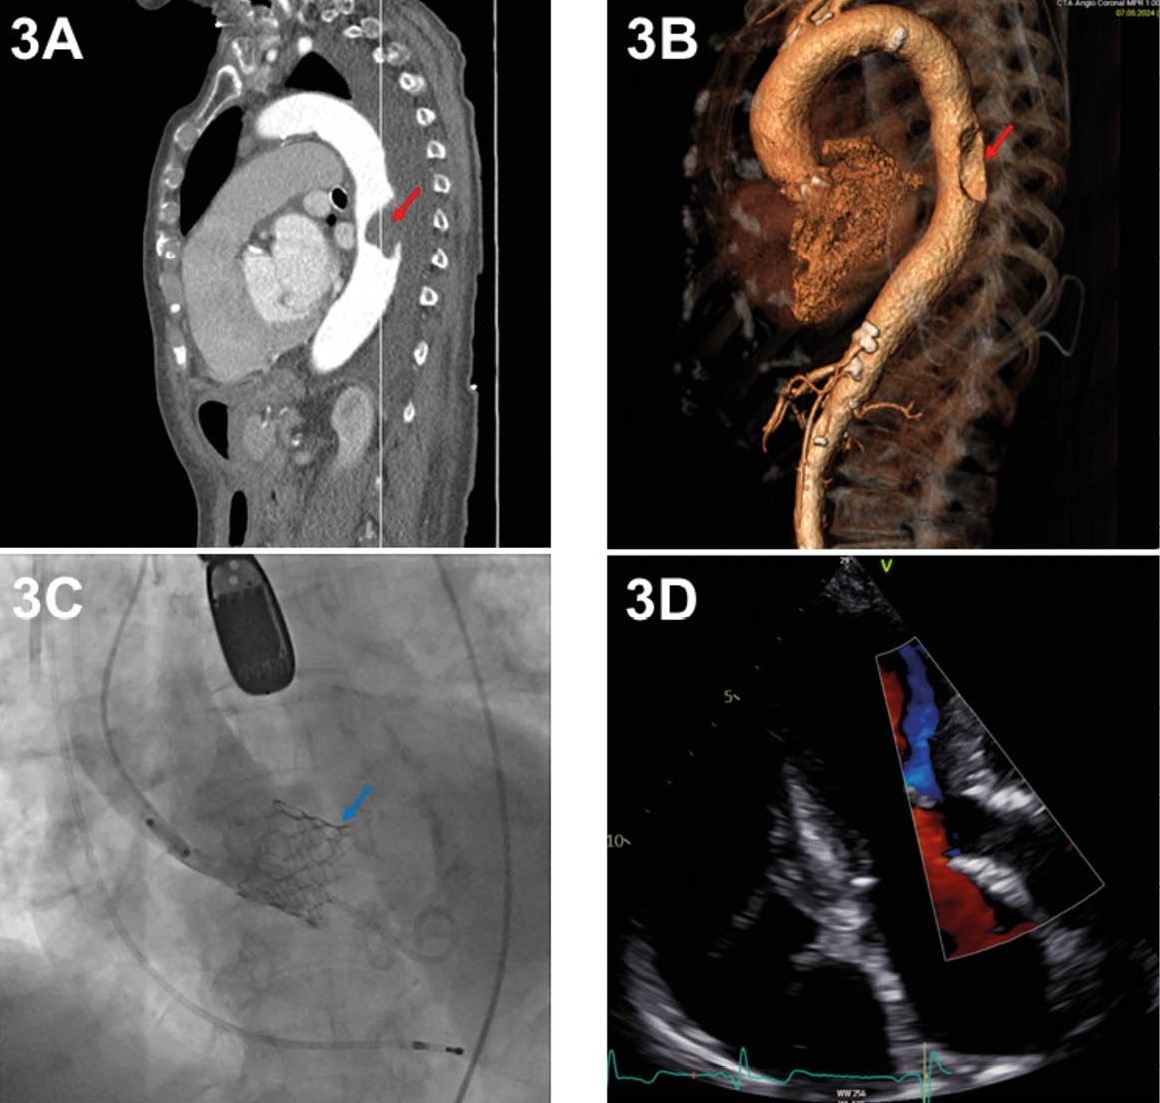

Ein 89-jähriger Patient stellte sich mit Dyspnoe NYHA III° (Die NYHA-Klassifikation (New York Heart Association) bewertet den Schweregrad der Luftnot) bei hochgradiger Aortenklappenstenose (AV-Gradient max/mean 65/42 mmHg; Der Aortenklappen-Gradient (AV-Gradient) bezeichnet den Druckunterschied zwischen dem linken Ventrikel und der Aorta und dient neben anderen Parametern zur Quantifizierung der Schwere der Aortenklappenstenose) in der Universitätsklinik für Kardiologie vor. Das Herzteam entschied sich für eine TAVI, jedoch schloss ein ausgeprägtes „kinking“ (Krümmung) der Iliakalgefäße und der Bauchaorta (Abbildung III 1A) den transfemoralen Zugangsweg aus.

Der Patient wurde daher für eine transaxilläre TAVI aufgeklärt und vorbereitet. Ein Jahr zuvor war aufgrund eines AV-Blocks III° ein linksseitiger Herzschrittmacher (HSM) implantiert worden (Abbildung III 1B).

In Intubationsnarkose und mit periprozeduraler transösophagealer Echokardiographie (TEE) wurde der Patient auf dem Rücken gelagert. Es wurde ein etwa 5 cm langer Schnitt zwischen der Mohrenheimschen Grube und der Mitte der Klavikula auf der linken Seite gesetzt. Trotz des liegenden HSMs gelang uns durch vorsichtige und sorgfältige Präparation die freie Darstellung der A. axillaris links (Abbildung III 1C). Anschließend wurden die A. axillaris bzw. der distale Teil der A. subclavia jeweils mit einem Vesselloop umschlungen. Die Punktionsstelle wurde mit zwei 5-0 Prolene-Tabaksbeutel-Nähten vorbereitet. Die Punktion des Gefäßes erfolgte in Seldinger-technik. Zunächst wurde eine 6-French-Schleuse inseriert, die in eine 18-French-Schleuse Sentrant (Medtronic Incorporation, Minneapolis, MN, USA) gewechselt wurde. Es erfolgte die Implantation einer selbstexpandierenden Evolut FX Klappe, Größe 34 (Medtronic Incorporation, Minneapolis, MN, USA) (Abbildung III 1D). Aufgrund des geringen Diameters des Zugangsweges wurde schleusenlos implantiert, das heißt, die 18 French Sentrant-Schleuse wurde zuvor entfernt. Die Klappe ließ sich problemlos positionieren und es verblieb weder ein Gradient noch ein paravalvuläres Leck (PVL, Undichtigkeit um die positionierte TAVI). Nach Extubation im OP-Saal wurde der Patient zur Überwachung auf die kardiologische IMC-Station verlegt. Der postoperative Verlauf gestaltete sich komplikationslos, sodass der Patient nach sieben Tagen in die Häuslichkeit in die Obhut seines ambulanten Pflegedienstes entlassen werden konnte. Aufgrund der deutlich verbesserten klinischen Situation und des nun bestehenden Rehapotentials wurde eine Anschlussheilbehandlung angemeldet.

Abbildung III: Fall 1

1A: CT-basierte 3D-Darstellung der Beckenachse und der gesamten Aorta mit massivem Kinking (rote Pfeile) mittels 3mensio-System.

1B: Röntgenbild des Thorax, der die Lage des Herzschrittmachers (HSM) zeigt.

1C: Freipräparierte Arteria axillaris (weißer Pfeil), umschlungen mit Vesselloops.

1D: Implantierte Evolut FX, Größe 34. (Medtronic Incorporation, Minneapolis, MN, USA)

Fotos: Klinik für Herz- und Thoraxchirugie, Klinik für Kardiologie und Angiologie, Klinik für Radiologie, Universitätsklinikum Magdeburg